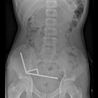

The 13-year-old boy was hospitalised after suffering four days of agony following his unusual snack, surgeons found around 100 magnets in his small and large intestine and had to remove dead tissue...